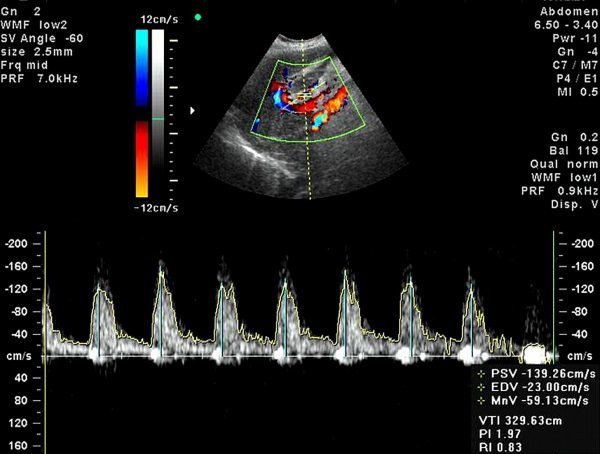

- Ультразвуковое исследование сердца. Позволяет более детально разглядеть пораженный орган, его строение, размер. Также удается определить диаметр аорты, толщину эндокарда, оценить функционирование клапана. УЗИ может применяться с допплером, что помогает изучить процесс кровотока из сердца в аорту.

- УЗИ сердца. Измеряется диаметр аорты, толщина эндокарда, строение и работа аортального клапана. Если створки не смыкаются до конца или в них присутствуют отверстия, это тоже можно разглядеть на УЗИ. При допплеровском исследовании изучается движение крови из сердца в аорту.

Обязательным видом диагностики является эхокардиографическое исследование, при котором обнаруживается гипертрофия левого желудочка, кальцификаты на створках клапана, изменение их структуры. Также можно диагностировать малую амплитуду раскрытия клапанных створок и оценить степень стеноза. При помощи ЭхоКГ можно оценить скорость кровотока и определить давление в легочной артерии.